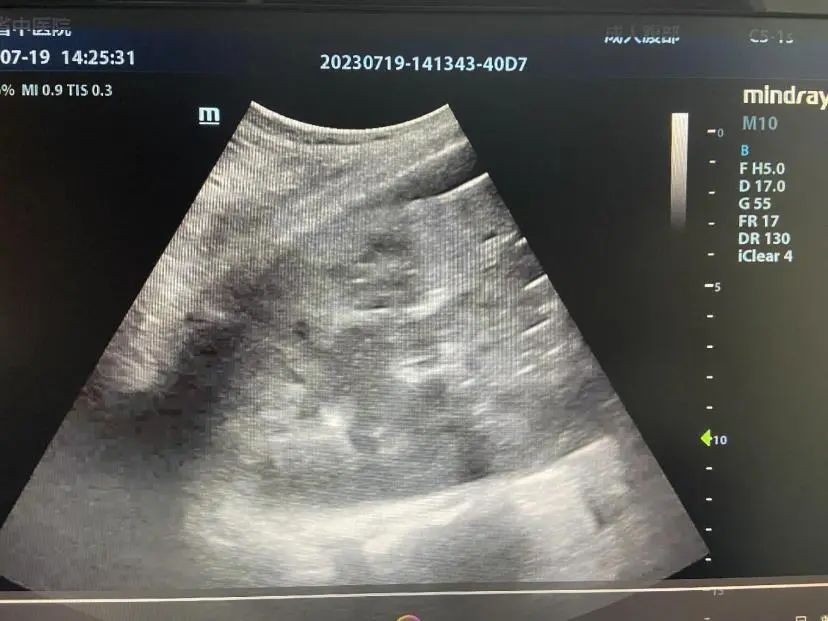

57岁的张先生因“咳嗽、咳痰、发热、头痛10余天”,已经在当地转院多家医院治疗,可是病情仍然不见好转,甚至出现了呼吸困难症状,最后因病情加重以“社区获得性肺炎(重症)、Ⅰ型呼吸衰竭”转入云南省中医医院ICU治疗。入院后,张先生的肺部CT检查结果提示:双侧胸腔中等量积液,左肺下叶实变肺内见空洞及多个气液平,考虑肺脓肿。随后,医生在床旁超声引导下行肺脓肿穿刺引流术,整个穿刺过程顺利,穿刺抽吸出脓性液体并送病检,同时向脓腔内注入美罗培南。术中未发生穿刺相关并发症,术后患者生命体征平稳,次日患者的呼吸困难的症状得到明显减轻,并且恢复自主进食。经过超声引导穿刺治疗患者病情已明显好转,不久即康复出院。

超声引导下行肺脓肿穿刺术